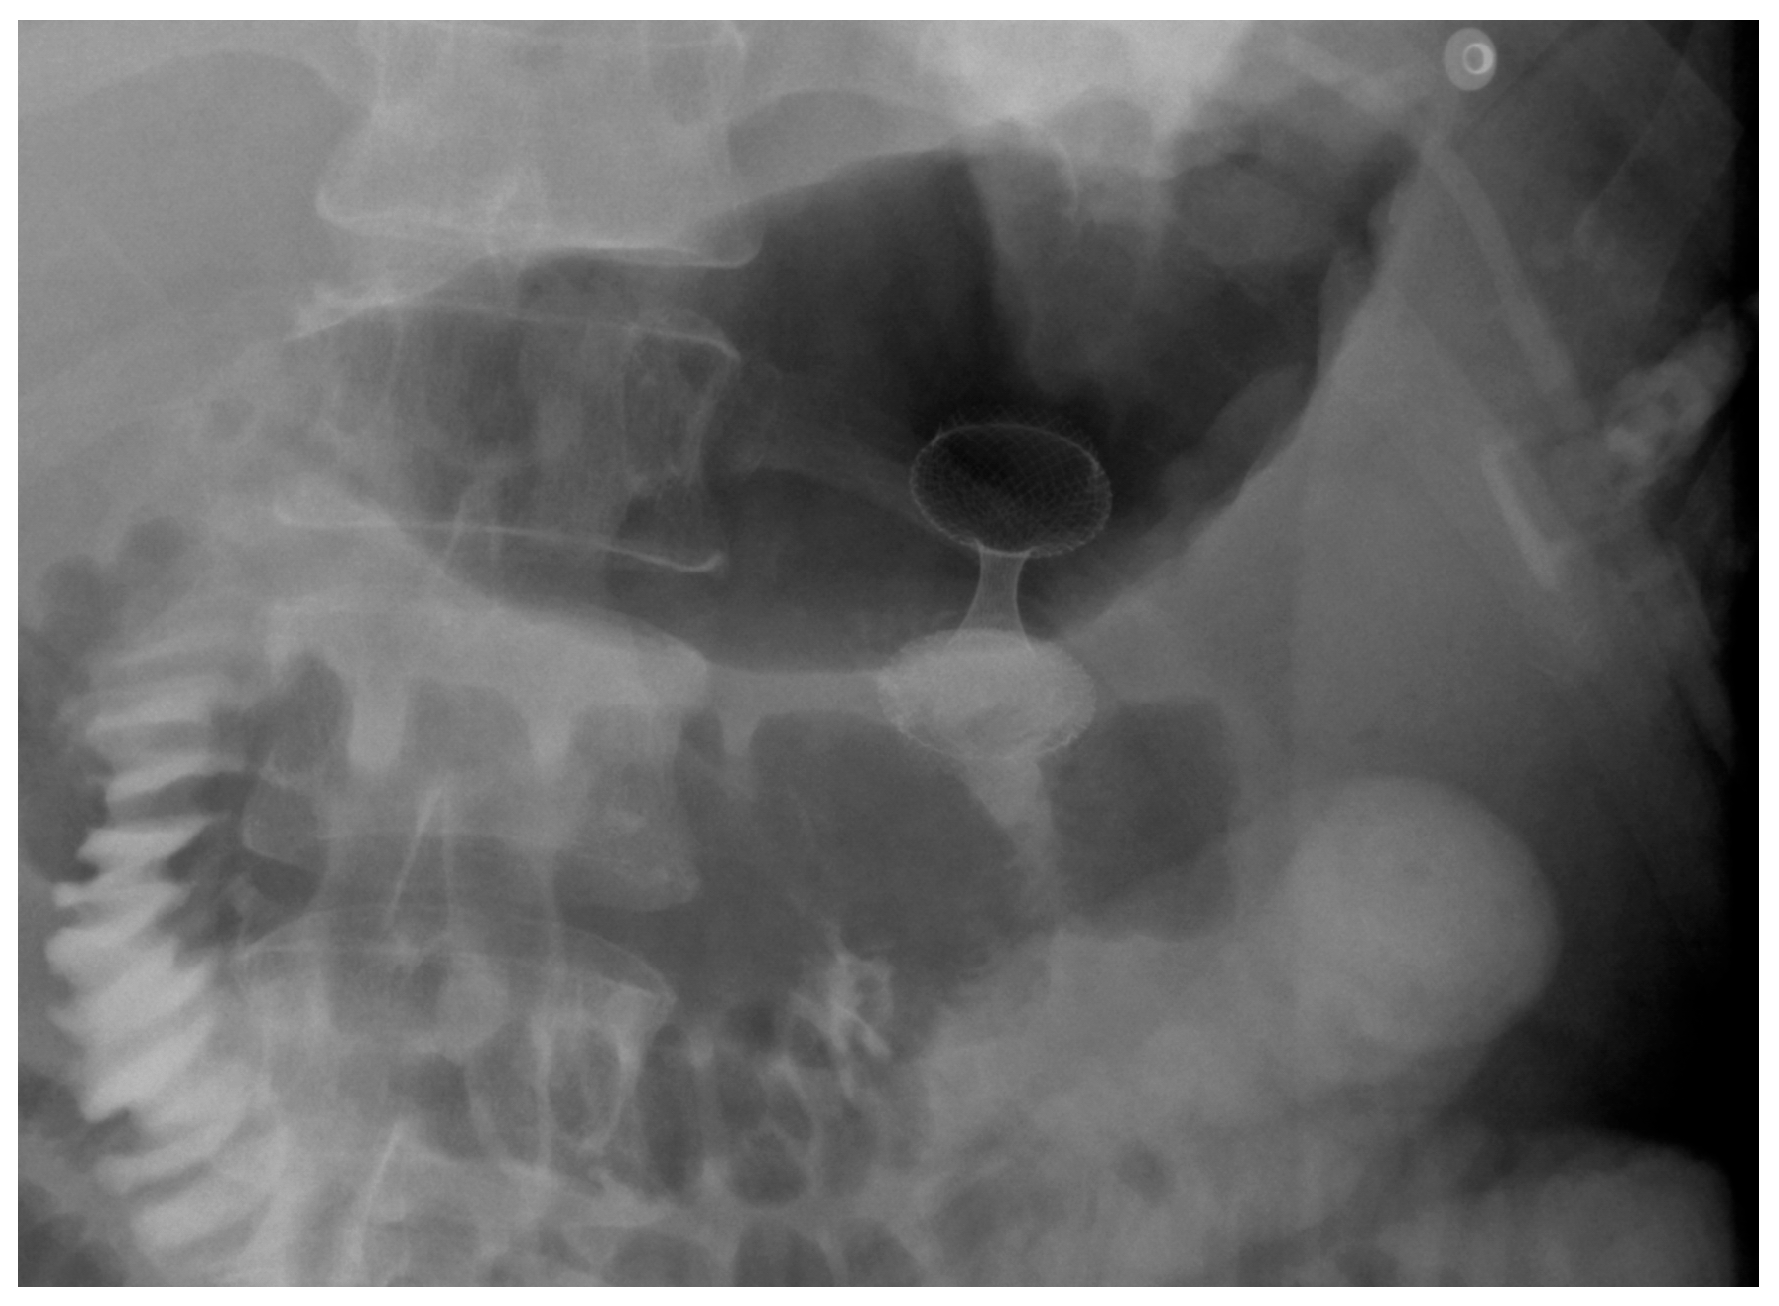

4. Gastroduodenal Tract—Gastric Outlet Obstruction

4.1. Malignant GOO

4.1.1. Role of Stent

Indications and Mechanism of Action

Efficacy and Adverse Events